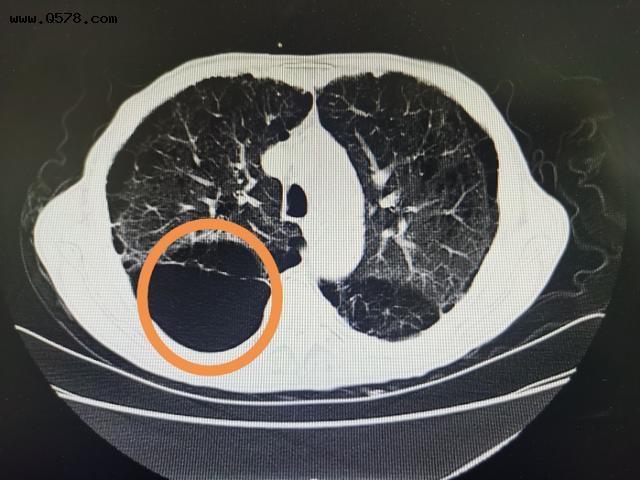

肺气肿CT图片

肺气肿CT图片,肺气肿x线图片

肺气肿的ct表现

肺气肿的ct图片

肺气肿的ct表现图片